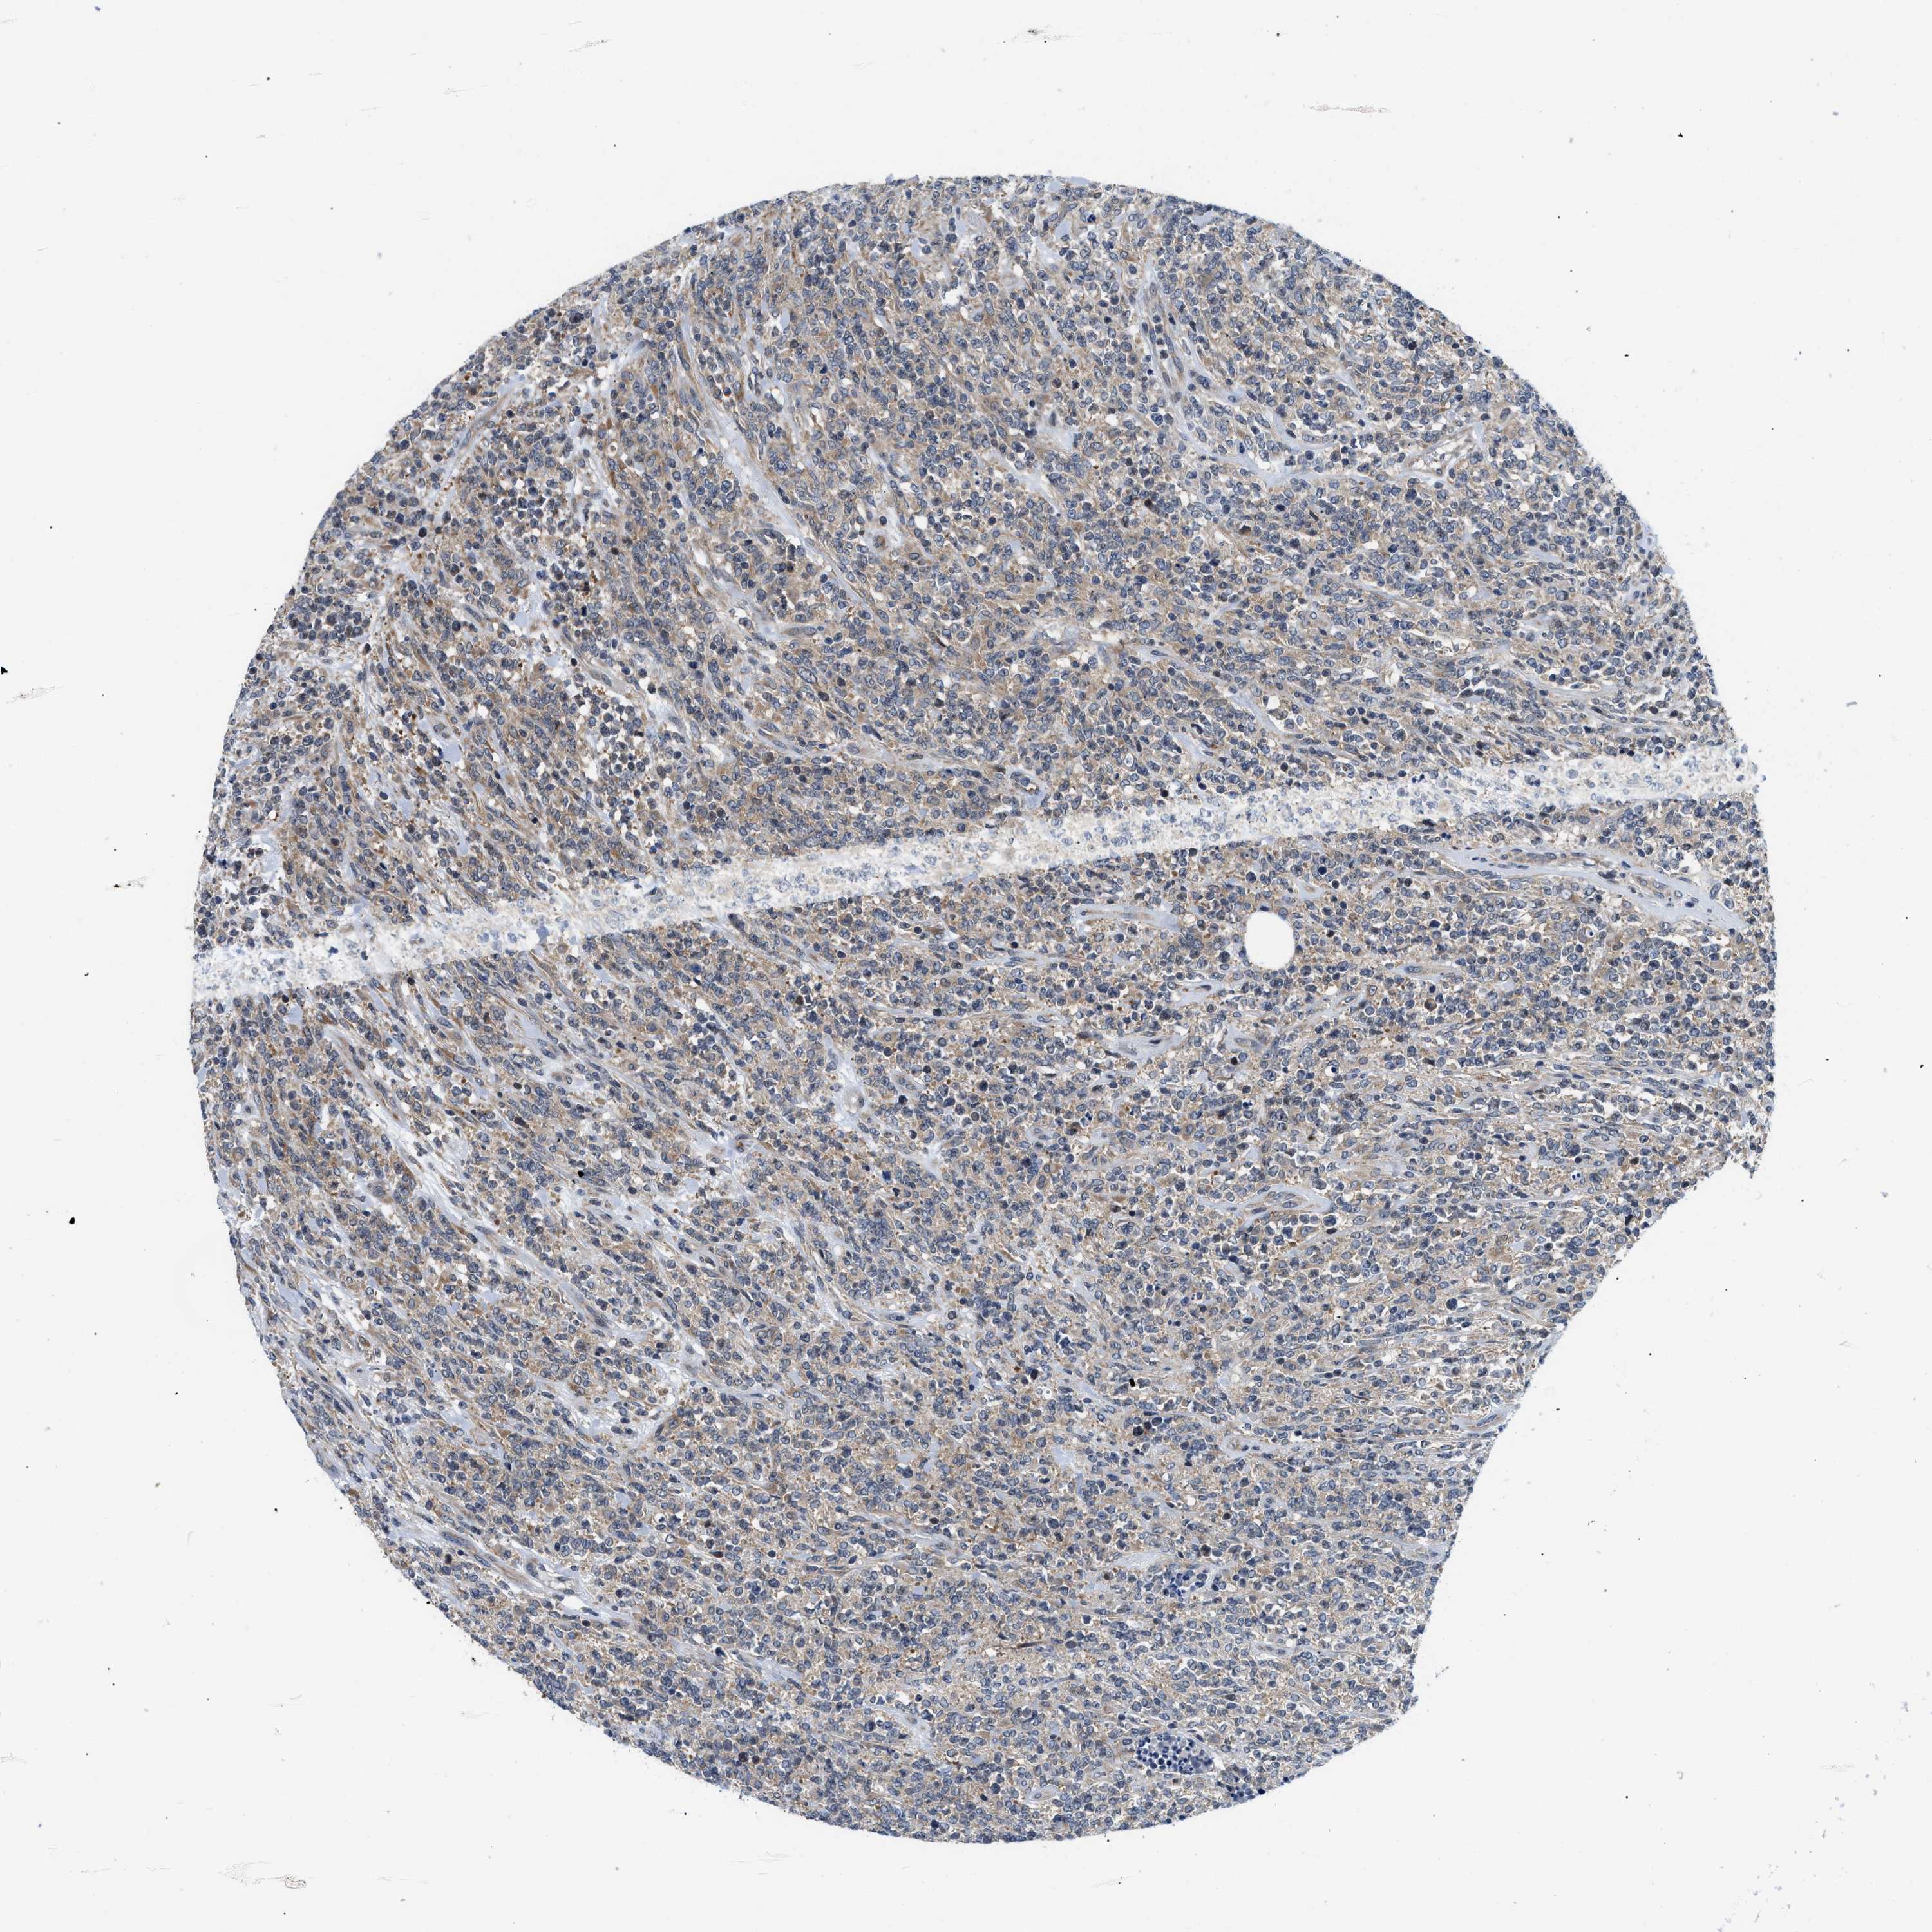

CANCER LYMPHOMA Show tissue menu

LYMPHOMA - Protein expressioni

A mouse-over function shows sample information and annotation data. Click on an image to view it in a full screen mode. Samples can be filtered based on level of antibody staining by selecting one or several of the following categories: high, medium, low and not detected. The assay and annotation is described here.

Antibody stainingi

Antibody staining in the annotated cell types in the current human tissue is reported as not detected, low, medium, or high, based on conventional immunohistochemistry profiling in selected tissues. This score is based on the combination of the staining intensity and fraction of stained cells.

Each image is clickable and will lead to virtual microscopy that enables deeper exploration of all samples and also displays staining intensity scores, fraction scores and subcellular localization as well as patient and tissue information for each sample.

Antibody HPA015788

Antibody CAB025983

Staining

High

Medium

Low

Not detected

Intensity

Strong

Moderate

Weak

Negative

Quantity

>75%

75%-25%

<25%

None

Location

Nuclear

Cytoplasmic/membranous

Cytoplasmic/membranous,nuclear

Hodgkin's disease, NOS

Malignant lymphoma, non-Hodgkin's type, High grade

Malignant lymphoma, non-Hodgkin's type, Low grade